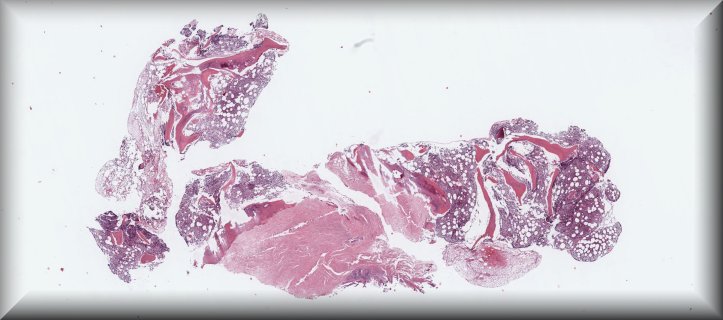

Caso 3.- Irene Salazar Saura, Josep Marí Alexandre, Sara Alemán Sánchez, Jose Joaquín Llopis Linares, Lara Navarro Cerveró, Esther Roselló Sastre.

Hospital General Universitario de Valencia.

Varón de 16 años con historia de un mes de evolución de astenia y palidez cutánea, que presenta cuadro adenopático inguinal y sospecha de trombosis venosa profunda, con síndrome leucoeritroblástico en sangre periférica.